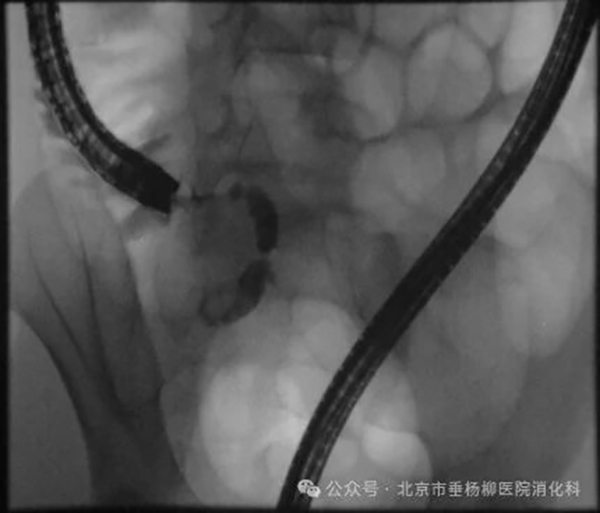

03、内镜下逆行阑尾造影:阑尾腔减压后,经导管注入适量造影剂,显示阑尾腔内的情况, 观察阑尾管腔形态、内径等。

01、经内镜阑尾腔插管,采用透明帽技术,使阑尾插管容易、安全。

02、阑尾腔减压:阑尾插管成功后,抽吸阑尾腔内的脓液,降低阑尾腔内的压力,防止阑尾腔压力升高导致的阑尾缺血、坏死。